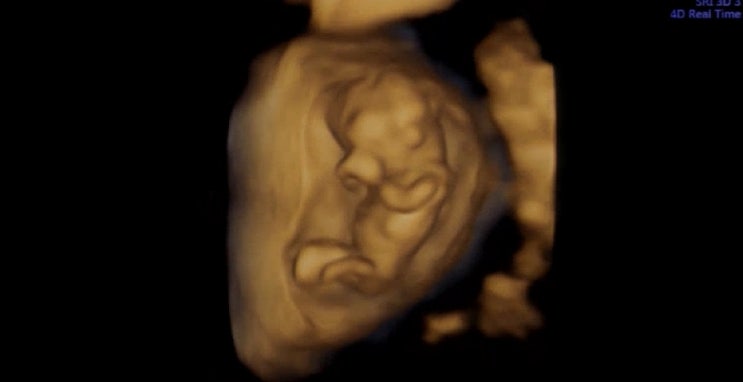

(임산부일기) 16주 아기성별 초음파, 2차 기형아 검사, 태동 느끼는 시기 20주 초음파

16주 2차 기형아 검사 초음파 #2차기형아검사 #16주초음파 #아기성별아는시기 #성별검사 16주 초음파랑, 2...

[임산부 일기] 12주 입덧 , 정밀초음파 , 1차 기형아 검사 14주 입덧사라짐 까지의 일기

11주 6일 11주 6일 ! 하루만 지나면 12주라서 , 1차 기형아 검사를 미리 예약해두고 정밀 초음파를 하러 갔...